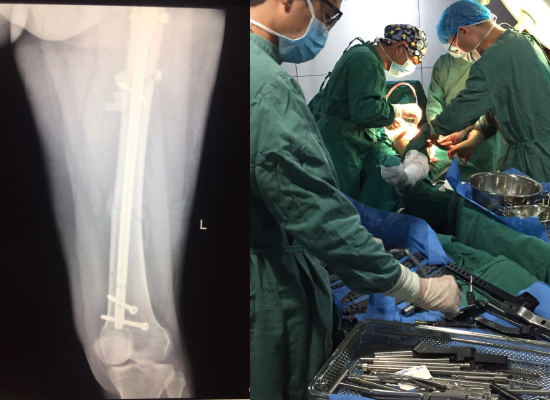

事故发生后,李女士很快被送到当地医院救治,诊断为“左股骨多段粉碎性骨折”,当地进行了清创消肿、打根骨牵引等对症处理。

DR片示股骨呈多段,骨折粉碎为多个骨块,复位难度极大,且复位后固定非常困难。”  骨科主任这样讲到。

手术后DR.png

满足手术条件后,骨科主任和医疗团队为李女士行左股骨多段骨折切开复位内固定术,手术历时四个小时,手术圆满完成。